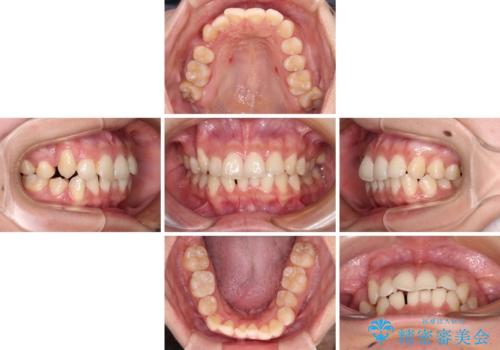

インビザラインによる矯正治療を希望されたため、八重歯改善のための抜歯矯正部分や上顎正中の大幅に位置移動は、補助装置やワイヤー矯正を併用し、その後はインビザラインにて行うこととしました。

ワイヤー矯正単体の方が期間や仕上がりは優位であるとご説明しましたが、インビザラインでの治療を希望されたため、補助装置併用の矯正治療を行うこととしました。

骨格的に下顎が左側に変位していたため、上下正中を合わせることは困難であることは分かっていましたが、可能な限り合わせることができました。